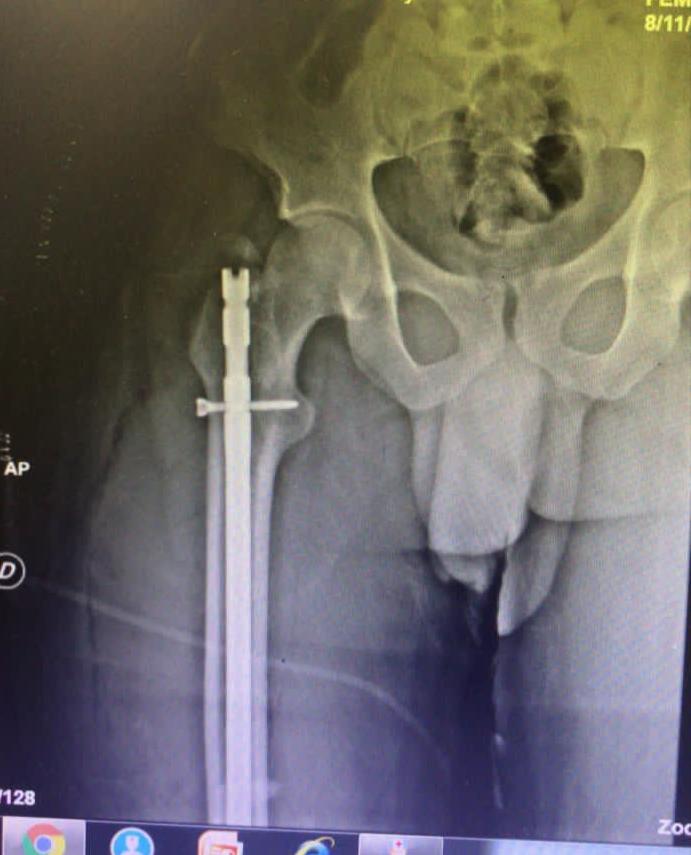

SANTO DOMINGO.- Durante este fin de semana el doctor Julio Landrón de la Rosa, director general del centro de salud junto a diversos especialistas realizaron una jornada quirúrgica donde se ejecutaron múltiples cirugías complejas de cadera, fémur, rodillas, columna, tobillo entre otras intervenciones.

“Todos los pacientes están evolucionando satisfactoriamente y reiteramos que los procedimientos quirúrgicos que realizamos son con el método Mínimamente Invasivo (MIPO) donde por vía láser y laparoscopica con pequeñas incisiones hacemos grandes cirugías, gracias al personal calificado profesional y los modernos equipos que contamos” agregó Landrón, quien también es presidente de la Sociedad Dominicana de Ortopedia.